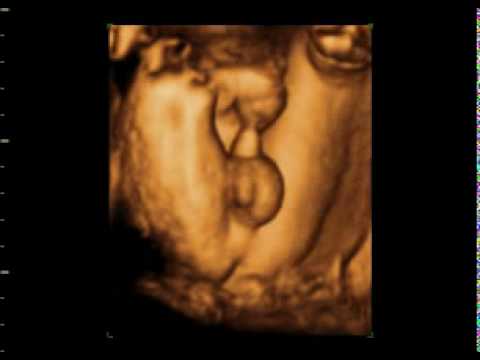

Mi lekarz określił płeć na prenatalnych już w 11tyg+3dni i to w dodatku na 90% (dziewczynka).Później sie potwierdzilo chyba w 16tyg.że dziewczynka i teraz na połowkowych że na 100%.Duzo zalezy przede wszystkim od umiejetnosci i doswiadczenia lekarza ale tez od sprzetu.Ja bylam u b dobrego specjalisty ktory wykonuje tylko i wylacznie usg prenatalne i ktory uczy innych lekarzy.U mnie sprawdzal przepływy i jakies kąty i na tej podstawie określił płeć.Z tego co wiem to płeć dopiero w 14 można okreslić. Wcześniej chłopczyk i dziewczynka wyglądaja tam tak samo. U mnie w obu ciążach po 18 tyg Jak sprzet jest dobry i lekarz sie zna to raczej nie ma mowy o pomyłce, a jak na 3D sprawdzi to na 100%

Ja nie mam wątpliwości![]()

Edit: zdjecie dziweczynki nie chce mi się oddać więc link : http://www.katarzynamlodzianowska.pl/images/galeries/2/zdjecie2-dziewczynka.jpg

U mnie mam nadzieję że się już nie zmieni że chłopak, zdjęcie siusiaka mam, ale wydaje mi się jakiś mały, pamiętam ze przy pierwszym synu nie miałam wątpliwości, wręcz się martwilam ze on taki wielki. Ale zupełnie inne ujęcie z innego kąta więc może dlatego.